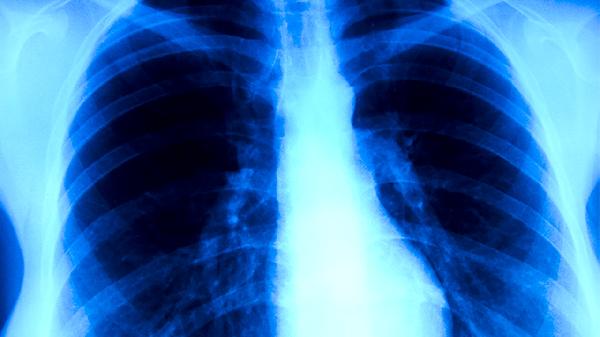

肺结核患者在规范服药期间一般可以游泳,但需满足无传染性、体力允许且水温过低等条件。肺结核是由结核分枝杆菌引起的慢性传染病,抗结核治疗通常需要6-9个月,游泳等适度运动有助于改善心肺功能,但需结合个体状况调整。